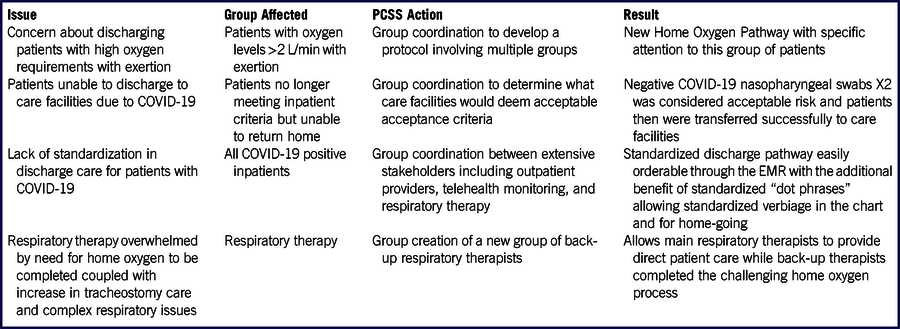

TABLE 1 Role of the PCSS in Identifying Issues and Solutions

The correlation upon univariate analysis of the analyzed variables with fatal outcome is listed in Tables 1, 2, 4.

We observed that different variables significantly correlated with the outcome: sex (P = 0.001), and age (P < 0.001), various comorbidities, assumption of ACEi (P < 0.001), and days of hospitalization (P < 0.001).

Analyzing symptoms upon admission, only dyspnea correlated with mortality (P = 0.001); fever did not correlate (P = 0.336), but the days of fever did (P < 0.001).

Among blood tests, C-reactive protein, D-dimer, and fibrinogen were significantly correlated with the outcome (P = 0.001).

At CXR, GGO with peripheral distribution, consolidation, pleural effusion, and the severity score showed a significant correlation with fatal outcome (P < 0.001).